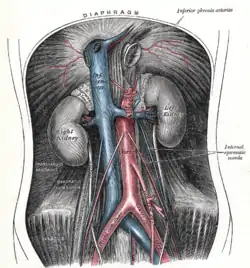

| Plate from Gray's Anatomy showing the abdominal aorta and the common iliac arteries | |